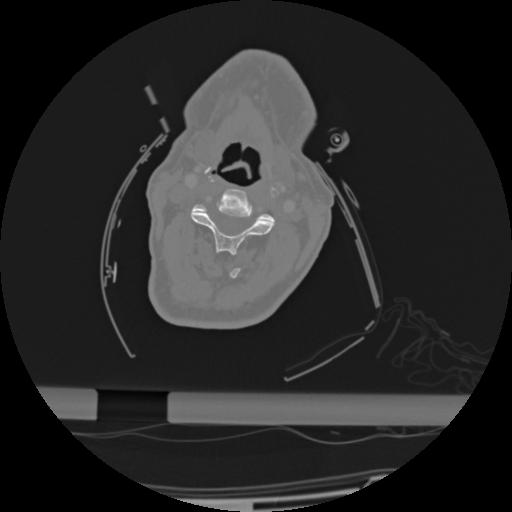

22 ANGIO,CE,Vol,0.5,ANGIO,,